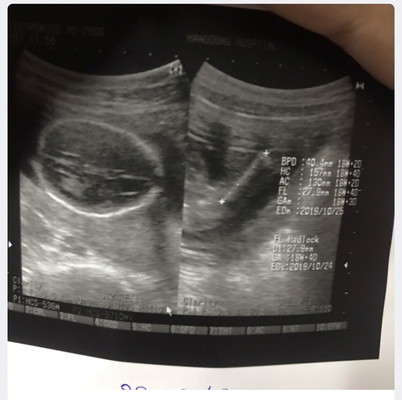

ภาพฝั่งซ้ายมือที่เป็นรูปวงกลมนี่คือส่วนไหนของน้องหรอคะ ฝั่งขวามือพอดูออกแต่ฝั่งซ้ายมือมองไม่เป็นเลยอะค่ะแม่ๆ

รูปซ้ายน่าจะเป็น รูปหัวของน้องค่ะ ถ้าดูจากเลขด้านขวานะคะ /BPD คืออการวัดความกว้างของศีรษะ /HC ขนาดเส้นรอบวงศีรษะ /AC ขนาดเส้นรอบท้อง รูปขวาน่าจะเป็นกระดูกต้นขาน้องค่ะ FL ขนาดความยาวกระดูกต้นขาค่ะ

ส่วนหัวของน้องค่ะ